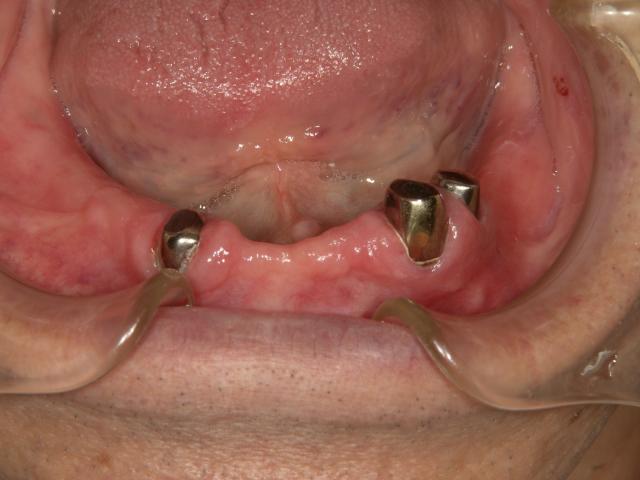

磁石を使用した金属床の入れ歯

2006/09/30

担当:院長

下の総義歯ですが、審美性と機能を考えて磁石を使用した設計で製作しました。

金属床の入れ歯 金属床の入れ歯

金属の針金を使用せずに食べたものも挟まりにくいです!自然感があり良好との事です!